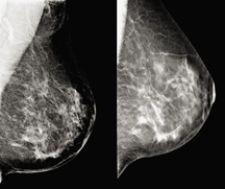

Because lower recall rates have high clinical significance and there is a corresponding reduction in the number of negative biopsies, technology that supports full-field digital mammography (FFDM) in reducing rates could prove extremely beneficial to clinician and patient alike.

Presented in the RSNA late breaking multicenter trial track were results from the first major multicenter study of digital breast tomosynthesis (DBT). According to lead author Elizabeth Rafferty, M.D., associate director of Breast Imaging at Massachusetts General Hospital, ROC analysis of 12 readers demonstrated statistically significant better performance in reading DBT with FFDM mammograms than FFDM alone.

“Across the spectrum of age and experience, every reader performed better,” noted Dr. Rafferty during Hologic’s RSNA Investor briefing. She estimates that tomosynthesis can reduce the screening recall rate in a normal screening population by 40 percent. “That is because tomosynthesis gives you the value of being able to correctly dismiss summation shadow or overlapping structures, more accurately characterize lesions and still see calcifications.”

In their R2 computer-aided detection product area, Hologic previewed the works-in-progress Quantra, a fully automated tool that can help assess breast density. According to Julian Marshall, director of Product Management and principal engineer, computed-aided detection, Quantra creates a model of the X-ray imaging chain to calculate the type of breast tissue, including density, penetrated at each pixel in the image. “The technology automates measurement of the total volume of both breast and fibroglandular tissue,” explained Marshall. Hologic is beginning clinical trials to determine if the volume of fibroglandular tissue provides a more accurate assessment of the correlation between breast density and a woman’s future risk of developing breast cancer than the current standard of calculating total percentage of breast density.

Findings from the study indicated that structured noise on cone-beam CT was minimal due to absence of overlapping tissue. Further, researchers found that breast anatomy was resolved on all images as skin, adipose, glandular regions, and that microcalcifications within cancers were clear. Additionally, because there was a lack of overlapping glandular tissue, detection of cancers based on morphologic assessment of tissue structures could be better compared with mammography.